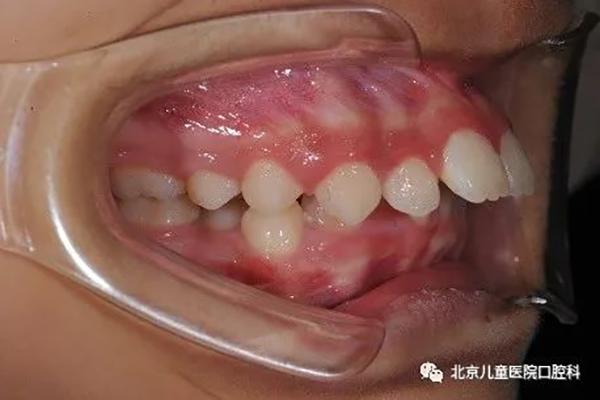

2、前牙严重前突,需要最大限度内收前牙,改善面下1/3美观。

治疗前